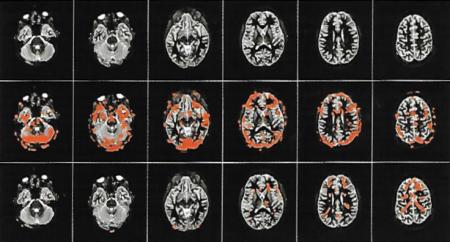

Who would have thought that learning about pain could be an effective therapy for chronic pain? This picture is proof that pain education works:

Image: Why Pelvic Pain Hurts: 2014 Louw, Hilton, Vandyken

- The first row in this picture is an MRI of someone who has had chronic pain for 3 years.

- The second row is the same person, and they have just completed a movement that gives them pain.

- The third row is the same person, doing the same activity, after learning about pain science for 30 minutes.